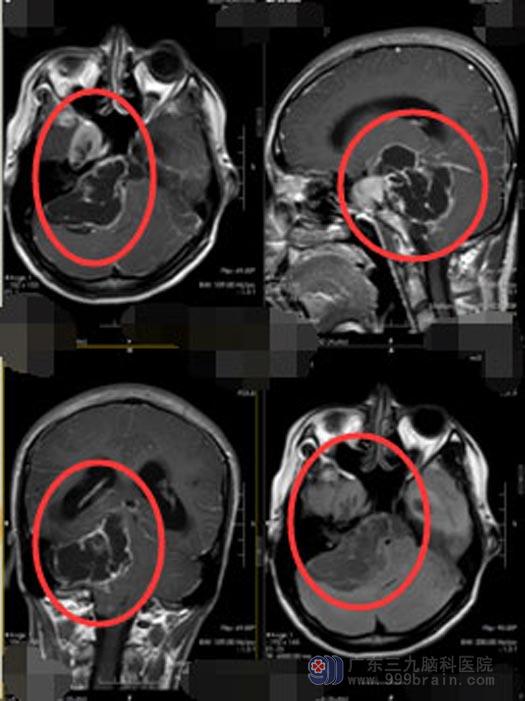

进一步脑部MR检查,结果显示:右侧桥小脑角-右中颅窝底示不规则囊性占位性病变,范围约7.4cm×6.7cm×6.2cm,侵及右侧内听道,局部与右侧乙状窦关系密切,且包埋邻近右侧海绵窦,结合DWI,考虑神经鞘瘤可能性大;头颅CT考虑右侧桥小脑角区占位:考虑神经鞘瘤可能,并幕上梗阻性脑积水。小吴头痛明显,考虑颅内高压,急诊行脑室外引流术;肿瘤跨越中后颅窝,手术难度大,风险高。